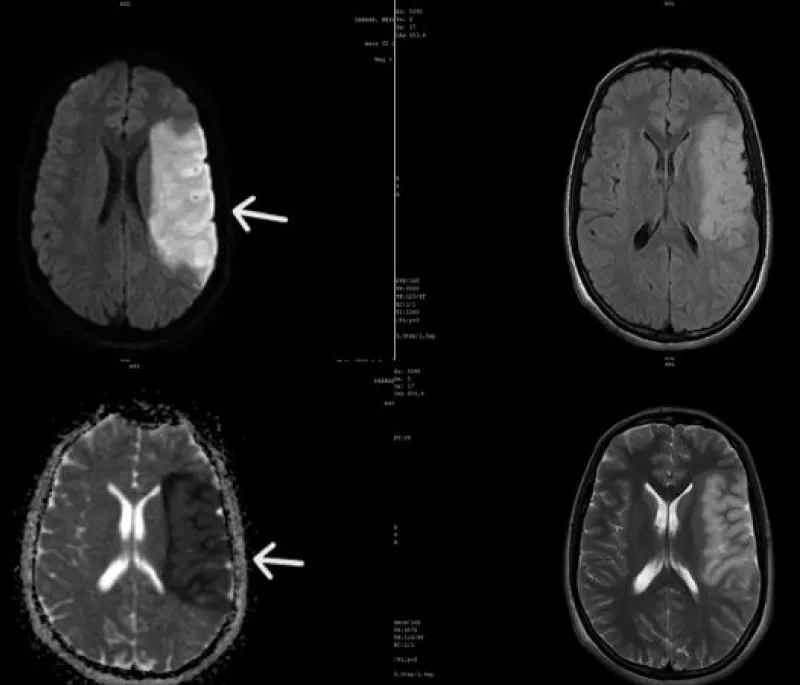

An urgent brain MRI was performed, revealing an extensive area of ischemia in the left middle cerebral artery territory with mass effect but no signs of hemorrhagic infarction (Figure 2).

Figure 2: Brain MRI showing a left deep Middle Cerebral Artery (MCA) stroke (white arrow), with an extensive ischemic lesion, noticeable mass effect, and no signs of hemorrhagic transformation.